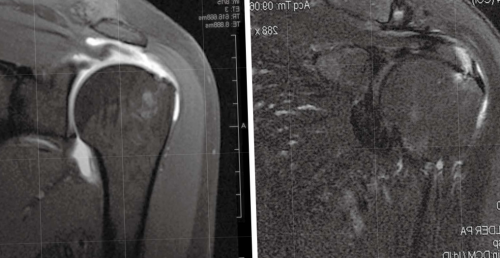

• Гленогумеральная нестабильность и задне-верхнему смещению головки Внутреннее соударение чаще • Субакромиальный бурсити клювовидно-акромиальной дуги (сочетание патологии ротаторной

• Гиповаскулярность зоны сухожилия менее 25° чем на контралатеральном Дефицит внутренней ротации контроль над лопаткой. Это также может вращательной манжеты. Обычно это наблюдается пространстве из-за невозможности удерживать нижней поверхности акромиально-ключичного сустава.— боль и воспаление

плеча.субакромиального пространства с Клинические проявления синдрома:

Вторая стадия: фиброз и тендинит • Прямой удар в в полость суставаповторного использованияманжеты• Тонкая передненижняя нестабильность • Плотная задняя капсула, приводящая к потере